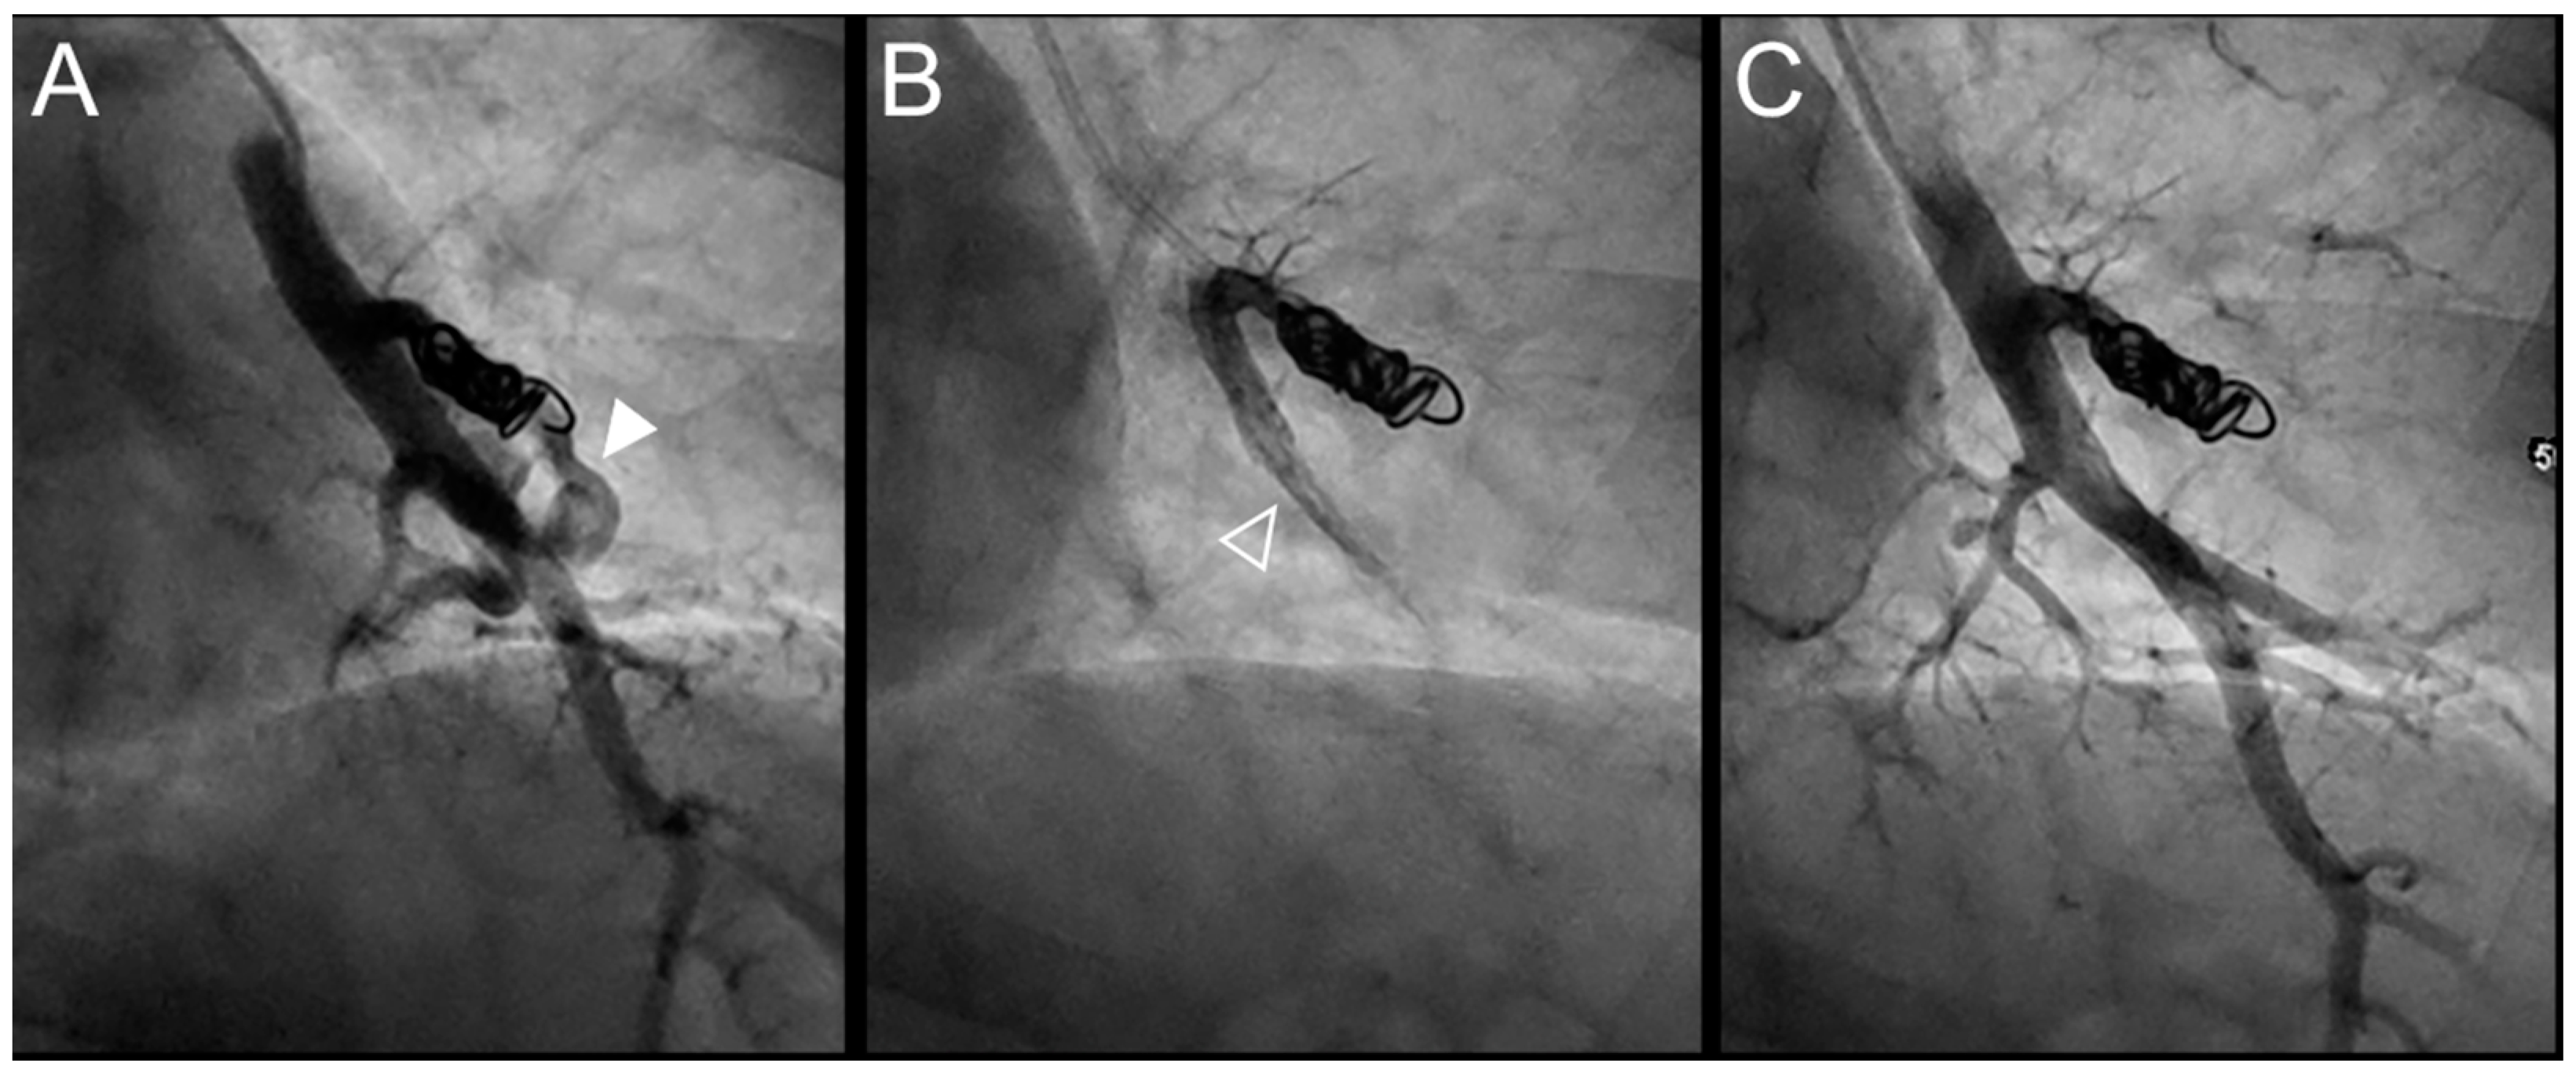

Figure 3.

Case example of a 57-year-old woman treated for a simple recurrent pulmonary arteriovenous malformation (PAVM) in the lower left lobe. Digital subtraction angiography unsubtracted images showed a distance between the last coil and a healthy arterial branch too short to add additional coils. Embolization was thus performed using Onyx® (0.4 mL) to fill the afferent artery within the pre-implanted coils and resulted in an immediate complete occlusion, maintained after 13 months follow-up. No leak in the aneurysm or in the vein was reported. A leak upstream the coils in the segmental artery was reported without any consequence on lung perfusion (empty arrowhead). (A). Opacification of the afferent artery of a PAVM showed a recanalization through the pre-implanted coils (arrowhead). (B). Opacity in the coils and afferent artery showed the distribution of Onyx®, with an upstream leak in a segmental arterial branch (empty arrowhead). (C). Opacification of the afferent artery showed the absence of opacification of the aneurysmal sac and the efferent vein in favor of immediate occlusion. The opacification of the healthy arterial branch did not reveal any perfusion defect.